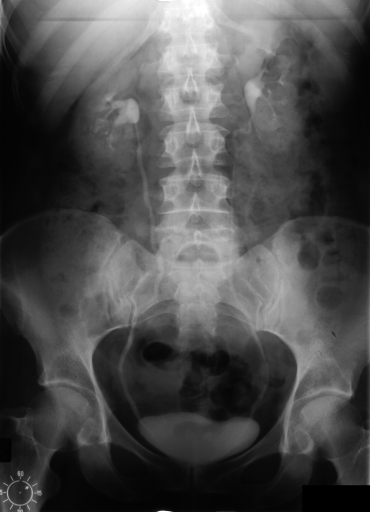

The IRMA dataset, supplied for the imageCLEF organization, had annotated codes were similar to domain expert knowledge [9, 12, 13, 14]. This database has been used by many researchers and is comprised of preset test and training portions, which enable direct comparisons of metrics. The IRMA codes (manually created by several clinicians) contains information on technical, biological and diagnostic traits of the image in a structured manner: TTTT-DDD-AAA-BBB. Each section is hierarchical meaning there is a least significant bit and most significant digit (Table 1). Sample IRMA images are depicted in Fig. 1.